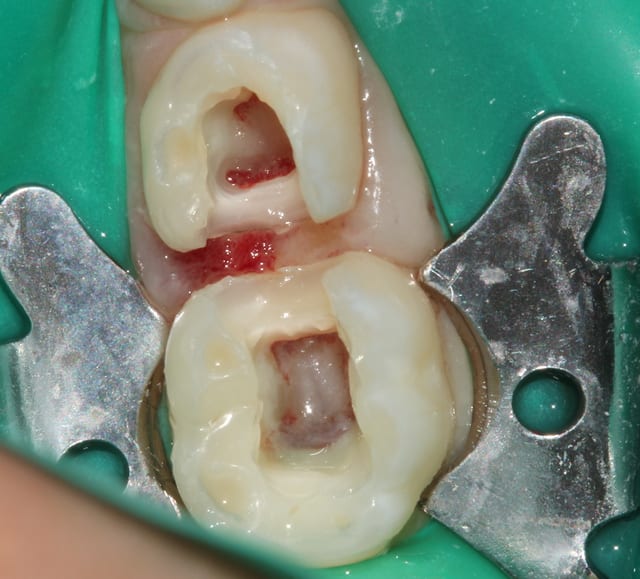

=> Crampons dentelés 12A ou 13A.

=> Technique "Split Dam" : deux perforations fusionnées dans ta feuille, bague sur la 5, tu étires jusqu'à la pointe canine.

Img 1613 vjgwcd - Eugenol

Img 1919 afymqb - Eugenol